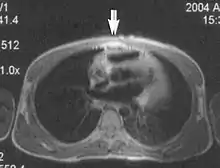

Motion artifacts

A motion artifact is one of the most common artifacts in MR imaging.[2] Motion can cause either ghost images or diffuse image noise in the phase-encoding direction. The reason for mainly affecting data sampling in the phase-encoding direction is the significant difference in the time of acquisition in the frequency- and phase-encoding directions.[1] Frequency-encoding sampling in all the rows of the matrix (128, 256 or 512) takes place during a single echo (milliseconds). Phase-encoded sampling takes several seconds, or even minutes, owing to the collection of all the k-space lines to enable Fourier analysis. Major physiological movements are of millisecond to seconds duration and thus too slow to affect frequency-encoded sampling, but they have a pronounced effect in the phase-encoding direction. Periodic movements such as cardiac movement and blood vessel or CSF pulsation cause ghost images, while non-periodic movement causes diffuse image noise (Fig. 1). Ghost image intensity increases with amplitude of movement and the signal intensity from the moving tissue. Several methods can be used to reduce motion artifacts, including patient immobilisation, cardiac and respiratory gating, signal suppression of the tissue causing the artifact, choosing the shorter dimension of the matrix as the phase-encoding direction, view-ordering or phase-reordering methods and swapping phase and frequency-encoding directions to move the artifact out of the field of interest.[1]